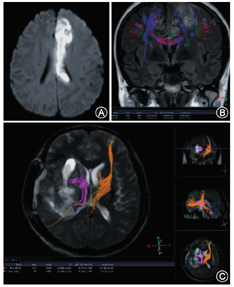

DTI是DWI技术的发展与深化,是当前唯一一种检测和追踪脑白质纤维束的非侵入性检查方法,可以定量评价脑白质的各向异性。组织中的水分子运动是多个方向的,也称水分子弥散的各向异性。DTI至少可以同时测量6个方向的水分子运动,从解剖和细胞水平,个体化地提供活体人脑白质纤维结构位置和走行特点的影像学信息[18]。目前临床主要用于指导脑外科手术,避免脑白质纤维束受损(图4)。